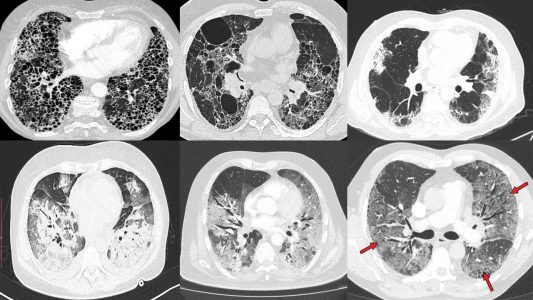

Η βασική διερεύνηση περιλαμβάνει την απεικόνιση των πνευμόνων με αξονική τομογραφία. Οι υψηλής ανάλυσης αξονικές τομογραφίες μπορούν να χρησιμοποιηθούν, για να βοηθήσουν στον καθορισμό του συγκεκριμένου τύπου διάμεσης πνευμονοπάθειας, εξετάζοντας τον τύπο και την εξάπλωση της νόσου στην απεικόνιση.

Σε προχωρημένη πνευμονική ίνωση οι πνεύμονες ενδέχεται να έχουν κυψελοειδή εμφάνιση εξαιτίας της εκτεταμένης καταστροφής κυψελίδων και της ανάπτυξης μικρών, κυστικών χώρων εντός του πνεύμονα, που μοιάζουν με μελικυρήθρα.